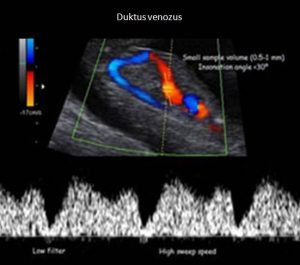

فحص دوبلر للقناة الوريدية: يتم عرض الأوعية الدموية التي تحمل دما مؤكسجا جيدا من الوريد السري إلى قلب الطفل لتقييم حجم الدم الذي يصل إلى الطفل. في الجنين ، تسمح القناة الوريدية للدم المؤكسج من المشيمة بتجاوز الكبد. في الحالات التي توجد فيها تشوهات دوبلر بسبب تقييد نمو الجنين ، سيزداد تدفق الدم في القناة الوريدية بشكل كبير.

لكن في حالات أخرى ، تزداد المقاومة تدريجيا إلى درجة الغياب المتقطع للتيار الانبساطي النهائي أو الغياب الدائم للتيار الانبساطي النهائي. في المرضى الذين يبدأون في إظهار عدم وجود تدفق متقطع في نهاية الانبساطي ، يكون السيناريو السريري عادة خطيرا بما يكفي ليتطلب علاجا للمرضى الداخليين. يشير عدم وجود تيار نهاية الانبساطي أو تيار عكسي نهاية الانبساطي إلى أن البيئة داخل الرحم تتعطل إلى النقطة التي يتأثر فيها تبادل الأكسجين وثاني أكسيد الكربون بشكل خطير. خاصة في التدفق العكسي للانبساطي ، يكون تبادل الأكسجين وثاني أكسيد الكربون ضعيفا لدرجة أن الجنين قد لا يكون قادرا على تحمل البيئة.

يعتمد التوقيت الأمثل للولادة في الأجنة المصابة بتشوهات دوبلر وتأخر النمو داخل الرحم على السبب الأساسي وعمر الحمل المقدر. بالإضافة إلى الشرايين السرية ، يمكننا تقييم الشريان الدماغي الأوسط في الدماغ لتقييم ما إذا كان الجنين يحاول حماية الدماغ في وسط بيئة فقيرة بالأكسجين. أكتوبر.